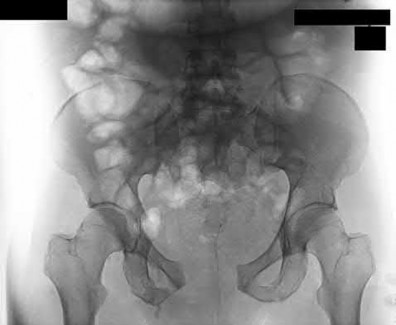

2. # A 35-year-old woman is involved in a head-on collision while driving. Initial radiographs are shown in Figures 8a and 8b. Injury to what vessel increases the risk for osteonecrosis of the injured bone?

5. Artery of the tarsal sinus Corrent answer: 4

The patient has a Hawkins type III talar neck fracture-dislocation with a risk of osteonecrosis ranging from 69% to 100%. Anatomic studies have shown that the artery of the tarsal canal supplies the lateral two thirds of the talar body.

The other vessels listed provide no significant contribution to the talus.